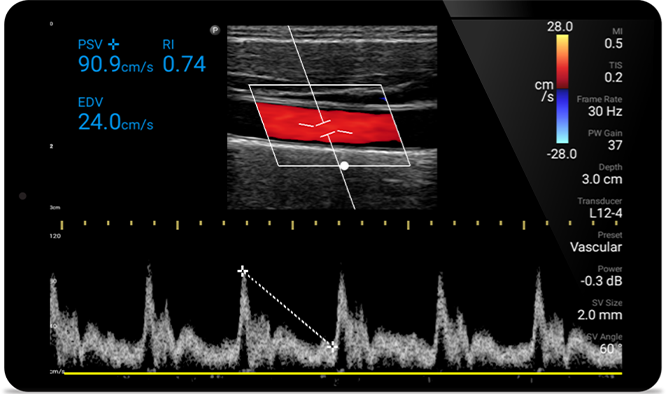

Onderzoeksresultaten binnen handbereik

Met Lumify kunt u de onderzoeksresultaten en -beelden van patiënten eenvoudig direct vanaf uw compatibele Android- of iOS-apparaat opslaan en openen. U kunt de resultaten zelfs delen met collega's voor een betere samenwerking.

Lumify kan helpen de subtiele details van een beeld zichtbaar te maken en afwijkende weefselstructuren bloot te leggen vanuit verschillende hoeken. Hierdoor kunt u met vertrouwen realtime beslissingen nemen, van diagnose tot herstel.